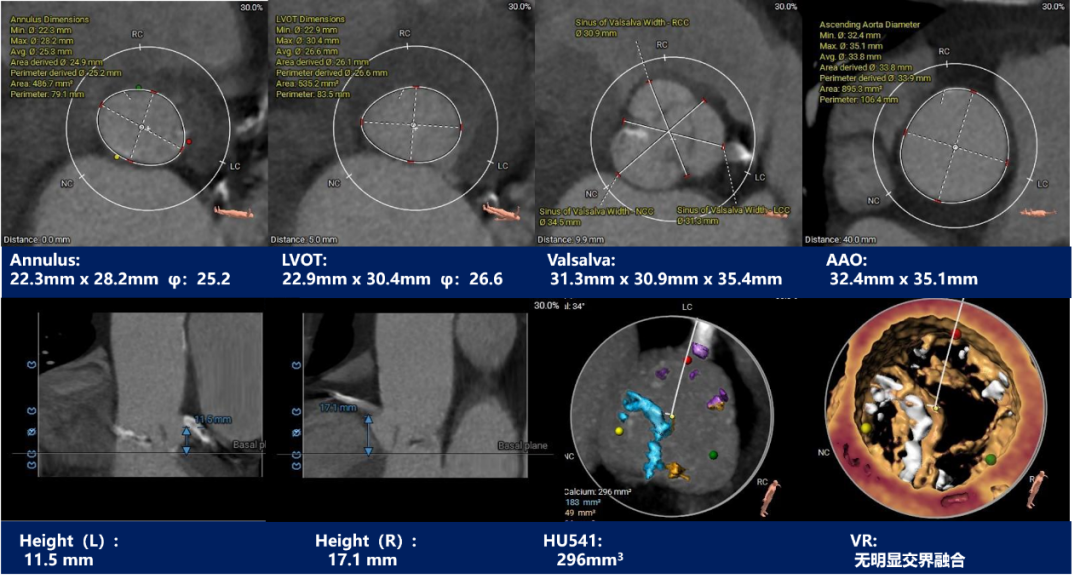

主动脉根部测量:

CT特点:功能性二叶瓣,瓣叶中度钙化伴增厚,钙化分布不均匀,主要分布于右无交界融合处,且无窦下钙化延伸至LVOT;流入端呈收口形态,瓦氏窦,窦管交界及升主动脉内径可,左右冠脉开口高度可,无冗长瓣叶;非横位心,心室壁肥厚,心腔偏小,双侧髂总动脉分叉前后可见多发钙化斑块,腹主动脉瘤,左髂总动脉有夹层病变。

CT特点:三叶式主动脉瓣,瓣叶轻度钙化伴增厚,钙化分布欠均匀,主要分布于无窦瓣叶边缘及其附着缘,瓦氏窦,窦管交界及升主动脉内径可,左右冠脉开口高度正常,无冗长瓣叶;横位心,心腔内径可,降主动脉及双侧髂总动脉分叉前后钙化严重。